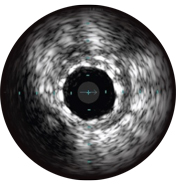

Внутрисосудистое ультразвуковое исследование (ВСУЗИ) — это технология, которая позволяет визуализировать кровеносные сосуды изнутри с использованием катетера. Данные изображения помогают оценить наличие и степень заболевания, форму и морфологию бляшки, контролировать положение проводника во время прохождения поражения и позиционирование стента после процедуры. Датчик, формирующий изображение, излучает высокочастотные звуковые импульсы, которые отражаются от стенок сосуда и улавливаются сенсорами, при этом интенсивность сигнала колеблется в зависимости от характеристик ткани. Система обрабатывает электронный сигнал и преобразует его в изображение.

ВСУЗИ помогает более точно определить степень и тип стеноза (т.е. минимальную площадь просвета (MLA), объем бляшки и кальций). Несмотря на то что ВСУЗИ позволяет выявить разрыв бляшки, наличие тромбов и диссекции, кальций наиболее распространен при рутинных ЧКВ. Оказывая большее влияние на стратегию стентирования, кальций отображается в виде очень ярких участков с акустическим затенением, которое блокирует изображение сзади. Также могут наблюдаться реверберации.